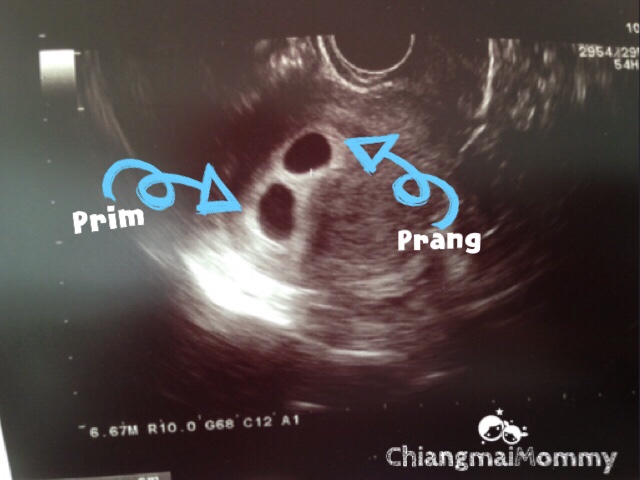

แนะนำการเลี้ยงดูลูกแฝด บทความ กิจกรรมข่าวต่างๆ หรือข้อมูลที่เป็นประโยชน์ เรื่องราว ประวัติศาสตร์ วิทยาศาสตร์ อื่นๆที่มีสาระไว้สอนลูกของเราค่ะ